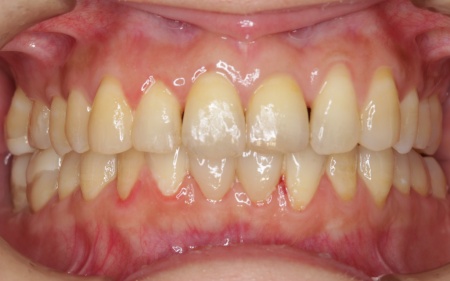

矯正治療が終了したあと、セラミックによる修復治療へと移行しました。 さらにすり減って形が不揃いになっていた下中央の前歯2本には、ラミネートベニアと呼ばれる歯の表面に薄いセラミックの板を貼り付ける方法を用いて形を調整しました。 以上の工程を順に進め、すべての治療を終了しました。 |

治療後